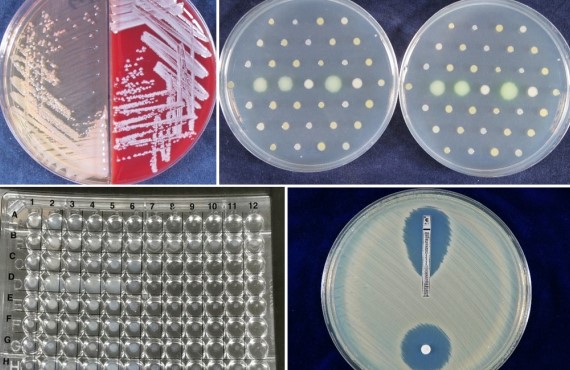

NIDB細菌資源庫團隊長期蒐集國內重要抗藥性菌株資料,熟悉細菌培養、菌種鑑定、抗藥性分析等技術,並透過微生物學、分子生物學、基因體等實驗進行後續加值分析。

真菌資源庫長期蒐集國內重要酵母菌及絲狀真菌菌株,熟悉真菌培養、菌種分子鑑定、臨床及環境檢體真菌檢測、CLSI標準抗真菌藥物敏感性試驗、小分子/化合物抗真菌效率測試、抗藥機轉分析、菌株親緣關係分析、斑馬魚疾病與毒性檢測模式等技術。

使用免疫缺陷小鼠建立特定感染病原動物模式,用此動物模式評估特定藥物或益生菌對不同感染性疾病的發生或症狀是否具抑制或改善功效。 實績: 1.抗真菌藥物臨床前測試:分析藥物或生物製劑抑制腸胃道念珠菌感染及對不同抗藥性念珠菌的影響 2.益生菌降低腸胃道病原感染測試:分析益生菌抑制腸胃道念珠菌或困難梭孢菌感染的效果